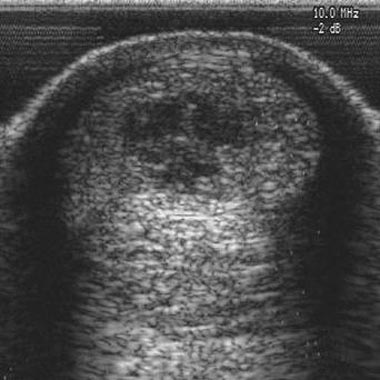

Both the bone marrow aspiration and the stem cell implantation will be demonstrated and attendees will be given the chance to practice the techniques. The course counts towards Continued Professional Development points and costs £175 per person plus VAT. You will also have the option to purchase a half price bone marrow aspiration kit and transport box so that you are ready to treat your first stem cell case. The deadline for registrations is 2nd June 2011. For more details on the course and how to book please click here, telephone 01865 922227 or visit www.vetcell.com/training/.More from